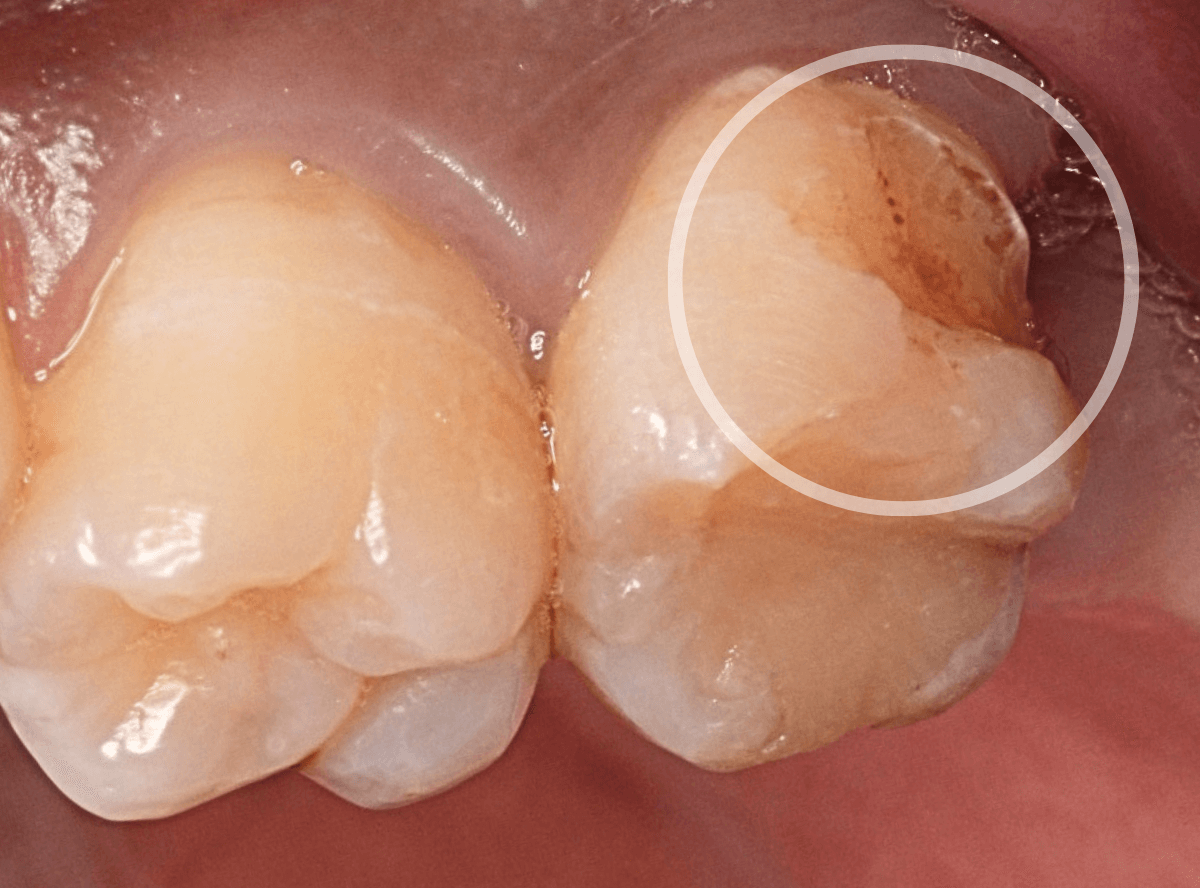

今回は「奥歯がしみる」という訴えで来院された患者さんのケースです。

知覚過敏の方は歯の側面がしみるケースが多いですが、今回は側面もしみるが、かみ合わせの面(咬合面)もしみるといいます。

しみる歯を拝見して「ちょっとこれは難しいケースかもしれないな」と思いました。

さて、なにが難しいかといいますと、

赤線の部分、歯の溝にあたる部分がかけてるというよりも、不自然に鋭角にえぐれている状態です。

くいしばりなどかみ合わせの力がここに不自然に集中してる可能性が高く、「何かスポーツなどされてますか?」とやんわりお聞きすると、心当たりがあるのか「職場で重い物を持ってくいしばる事が多いです」との事でした。

レントゲン写真で歯を確認します。

特に中に異常はなさそうですが、油断はできません。

このように大きな力がかかった歯にはレントゲンや見えない傷がついてたりする事もあります。

すると、不定期にしみや不快感が起こる事もあり、原因がわからず途方に暮れてしまう事もあるのです。

今回は幸運にもえぐれている部分にレジンを薄くつめる事で症状はかなり緩和されましたが、かみ合わせで短期でレジンが剥がれてしまう事も大いに考えられます。

できれば、マウスピースを作製し、日中も歯を保護してほしいですが、仕事中は難しいそうです。。。

状況を説明し、定期的に経過観察に来院してもらう事になりました。